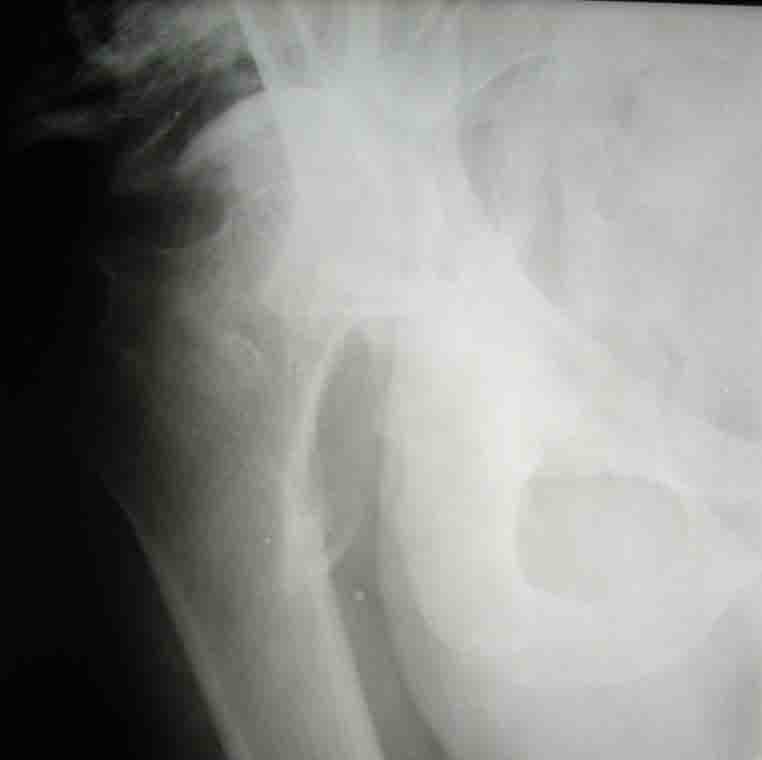

Уважаемые коллеги! На консультацию пришел молодой человек 23 лет с застарелым задним вывихомбедра. После травмы прошло 2,5 ГОДА.

Были переломы бедра и голени на этой же стороне, которые благополучно срослись после остеосинтеза. вывих бедра был пропущен. В настоящее время ходит без дополнительной опоры, есстественно, сильно хромает, выражен болевой синдром, парез седалищного нерва. Сформировался неоартроз в подвздошной области, виден неправильно сросшийся перелом задней колонны, сгибание в суставе до 80.

Что делать? Честно говоря, на таких сроках опыта лечения подобных больных нет (мах 8 мес). Постепенно низводить аппаратом и затем ставить эндопротез там где должен быть сустав? Или ставить протез выше истинной впадины с укорочением конечности, а затем удлиннять бедро или голень? У кого есть подобный опыт, подскажите?